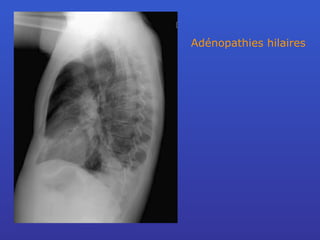

Adénopathies hilaires

TROPISME LYMPHATIQUE DE LA SARCOÏDOSE

Réponse SARCOIDOSE

Définition Granulomatose systémique diffuse de cause inconnue La lésion pulmonaire initiale est une alvéolite  lymphocytaire et macrophagique. Secondairement, formation de granulomes. paroi des alvéoles le long des bronches dans les septas interlobulaires

Stades Stade 0 : thorax normal Stade I :  adénopathies hilaires Stade II : adénopathies + atteinte pulm. StadeIII : atteinte pulm. sans adénopathies Stade IV: fibrose pulmonaire